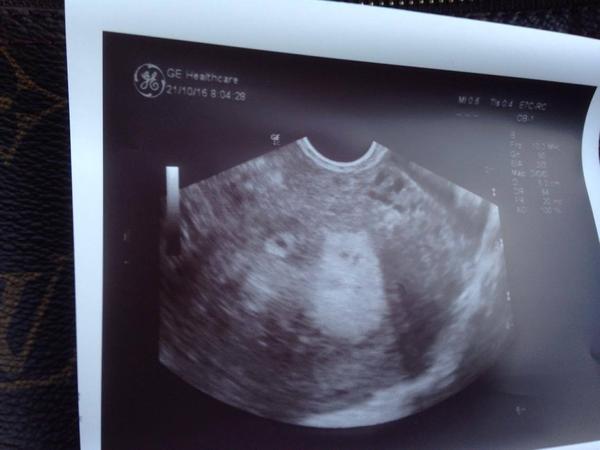

Holky, já jsem tak nesmírně šťastná.....ještě je to hodně brzy...ale to malé očičko nalevo hlásá....halooo...já jsem tady ....milujte mě...:o)))))